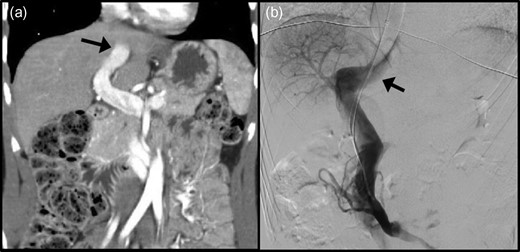

Pre-operative blood tests showed normal liver biochemistry and post-prandial hyperammonaenia (162 μmol/L: normal 16–60 μmol/L). Doppler ultrasound and computed tomography (CT) demonstrated a large communication between the left portal vein and the left hepatic vein with a patent and hypoplastic portal bed (Fig. 1a). Owing to the calibre and flow of the shunt, endovascular occlusion was not feasible (Fig. 2). Surgical treatment by a two-stage laparoscopic approach (partial occlusion followed by division) was subsequently planned. Pre-operative ICG clearance was measured as per institutional protocol (PDR: 5.5% min−1 and R15:43.8%) [6].

Radiological assessment of the patent ductus venosus (PDV) by (a) computed tomography and (b) digital subtraction angiography. Black arrow: PDV traversing towards the inferior vena cava.